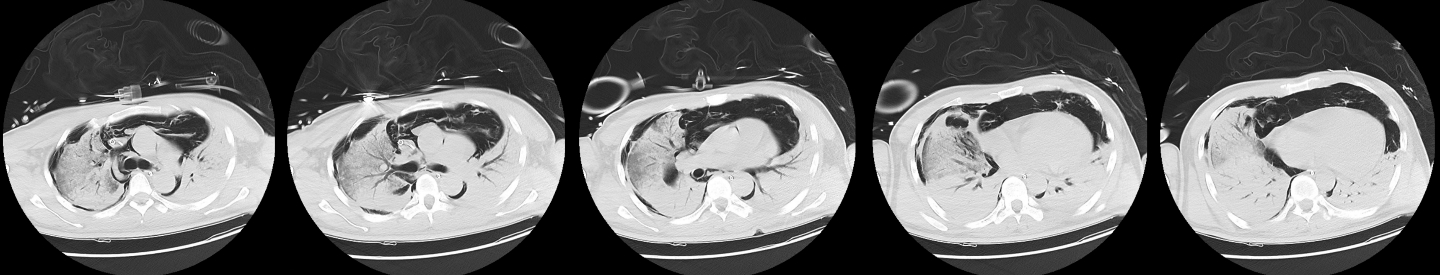

1 病例资料2024-11-15,某工地操作间有值班人员3人,分别为上铺(距地面1.8 m)A某,下铺(距地面0.4 m)B某、C某,事发当天为午休时间,设备出现故障,下午14时维修人员D某进入操作间维修,并将门窗打开,完成维修操作;事发后24 h内4名患者均出现不同程度的恶心、呕吐等消化道症状,起初考虑可能与食物中毒有关,前往当地医院就诊,完善血便常规、胸腹CT等相关检查未见明显异常,在医院给予吸氧补液静卧留观,留观期间4人先后出现不同程度的咽痛、咳嗽、胸闷、憋气等不适,吸氧不能缓解,再次行胸部CT检查示双肺弥漫性改变,间质改变可能,考虑为吸入有毒有害气体,后经采样检测操作间气体残留为全氟-4-甲基-2戊稀[Perfluoro(4-methylpent-2-ene),D1](D1纯度99.92%),导致急性呼吸窘迫综合症(acute respiratory distress syndrome, ARDS)。参照2002年职业性急性有机氟中毒诊断标准[1],A某诊断为急性中度有机氟气体中毒,B某、C某、D某诊断为急性重度有机氟气体中毒(PaO2/FiO2 < 100 mmHg,1 mmHg=0.098 kPa)。立即给予大剂量(120 mg)甲泼尼龙琥珀酸钠治疗,同时补充多种微量元素,加用甲钴胺、硫辛酸,钙剂解毒,后续加用特殊解毒剂乙酰胺治疗。治疗1周后,上铺的A某胸闷、憋气症状较前好转,影像未见明显进展,但患者仍遗留有间断气短症状;其余人员病情持续恶化,出现呼吸衰竭,转入重症医学科,给予气管插管接呼吸机辅助通气,维修人员D某上呼吸机后能基本维持,但不能脱机,继续观察患者病情变化;而下铺患者B某、C某症状不断加重,即使给予呼吸机治疗低氧状态仍未见明显改善,于2024-11-29转入本院进一步治疗。B某、C某入本院时查体:双肺叩诊呈清音,双肺呼吸音粗,可闻及干湿性啰音,具体指标见表 1,图 1、2为肺部影像进展情况。入院给予镇静镇痛、机械通气及抗感染、抗炎、抑酸等治疗,呼吸困难仍持续加重,存在难以纠正的低氧血症及高碳酸血症,表现为ARDS,有体外膜肺氧合(extracorporeal membrane oxygenation, ECMO)治疗指征,参考国内外相关救治经验[2-6],给予患者静脉-静脉ECMO(veno-venous extracorporeal membrane oxygenation, V-V ECMO)治疗,具体参数见表 2。

| 图 1 B某发病第1、3、10天胸部CT |

| 图 2 C某发病第1、3、10天胸部CT |